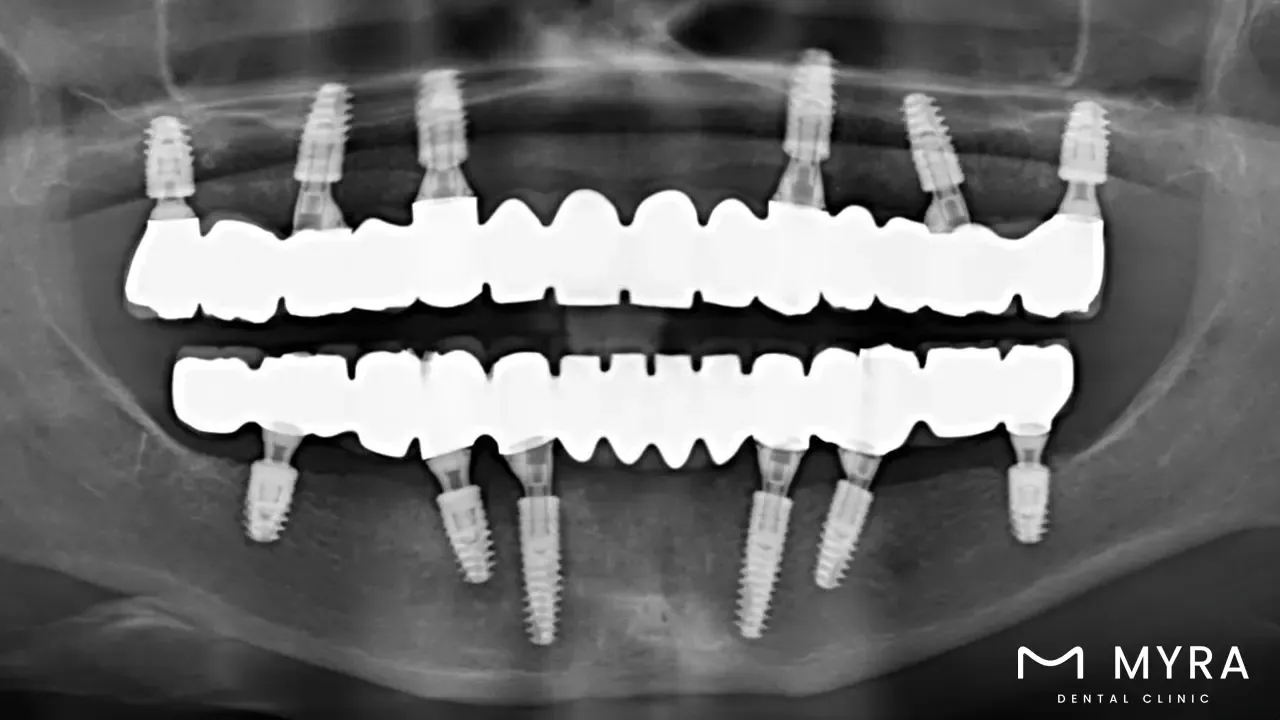

Whole mouth implants, referred to as complete tooth restoration, are a dental operation that entails using dental implants to change all teeth in the upper jaw as well as the lower jaw. Whole mouth implants are a form of restorative material created to satisfy every patient's unique demand while restoring the function and aesthetics of the teeth. Careful investigation of the individual’s dental health, surgical placement of the implants, and attachment of the prosthetic teeth are all milestones in the process of having full mouth implants. Individuals who have lost a significant number of teeth or who have serious dental problems that demand substantial treatment are often advised to get full mouth implants.

The process of getting full mouth implants includes several steps, including a thorough evaluation of the individual’s oral health, the surgical placement of the implants, and the attachment of the prosthetic teeth. The dental implants are customized to meet the specific needs of each patient, and the prosthetic teeth are designed to closely copy the appearance and functionality of natural teeth.

A full mouth implant is a comprehensive dental procedure that involves the replacement of all or most of the teeth in both the upper and lower jaw with dental implants. This treatment is suitable for individuals who have lost a significant number of teeth or are experiencing extensive tooth decay, gum disease, or other dental issues. The procedure typically involves the surgical placement of multiple dental implants throughout the jawbone to provide a stable foundation for the prosthetic teeth. Full mouth implants offer numerous benefits, including improved chewing function, speech, aesthetics, and overall oral health. The average cost of a full mouth implant can vary depending on factors such as the number of implants required, the complexity of the case, the type of restoration chosen (e.g., implant-supported dentures or individual crowns), and any additional treatments necessary, such as bone grafting or sinus lift surgery. On average, the cost of full mouth implants ranges from £3200 to £26800. It is important to consult with a dental professional to assess your specific needs and receive an accurate cost estimate based on your unique circumstances.

Entire mouth implantation entails an extensive examination of the patient's oral health and treatment objectives. The installation of numerous dental implants throughout the jawbone, and the affixing of a custom dental prosthesis to the implants. A visit with a dental expert is usually the first step in the process to ascertain whether the individual in question is an appropriate candidate for the operation. The dental implants are then surgically implanted into the jawbone while being sedated or given a local anesthetic. The customized dental prosthesis is attached to the implants after healing and osseointegration, creating a functional and realistic-looking tooth replacement.